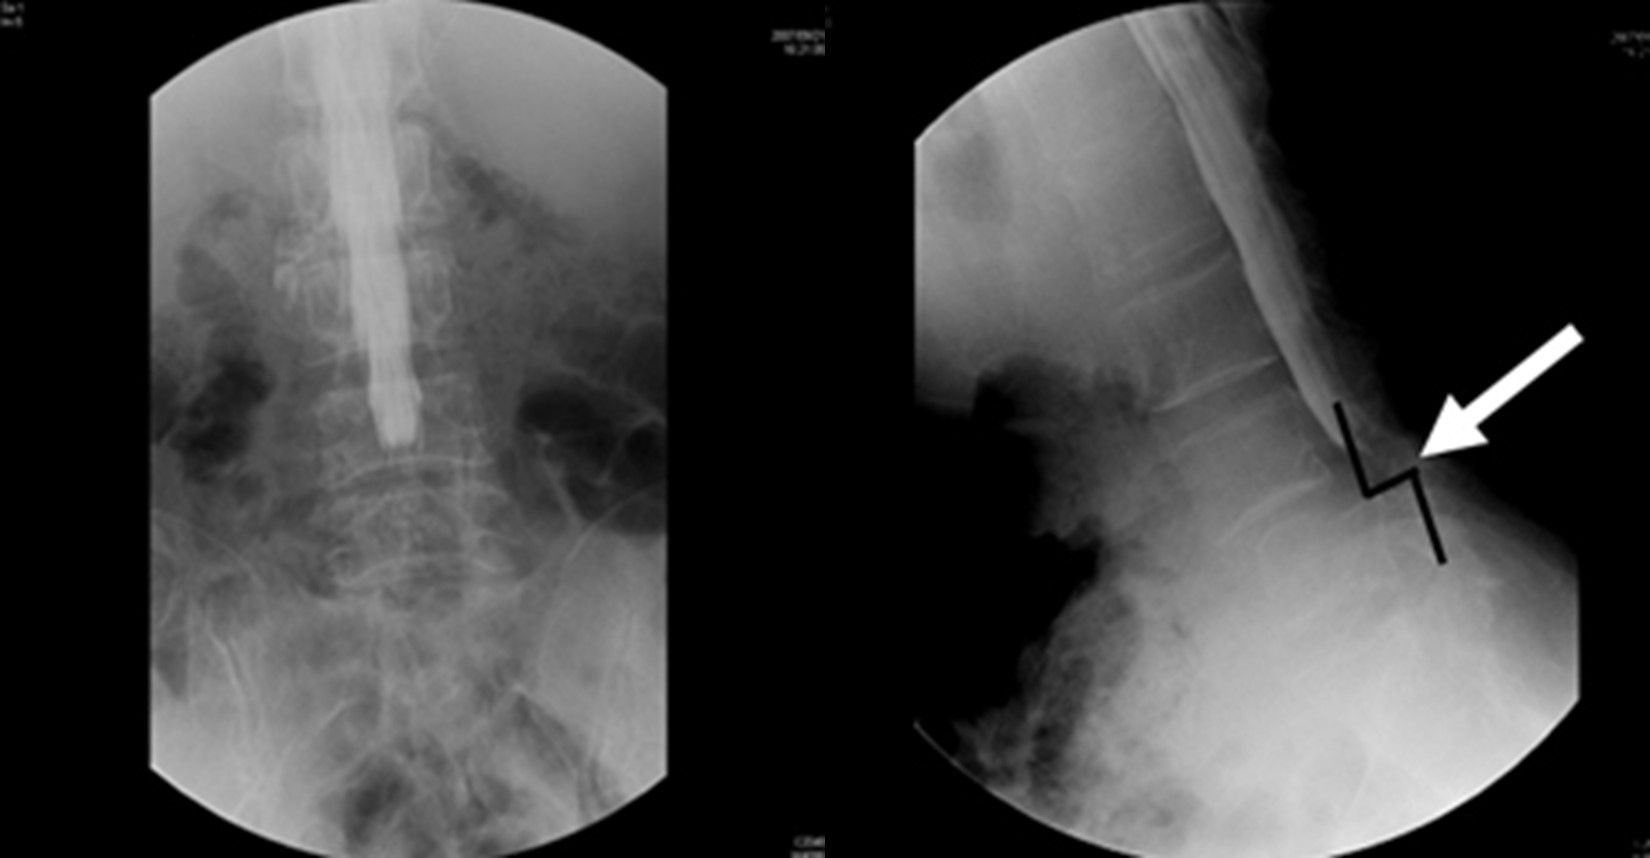

図 手術前:階段状に脊椎(せぼね)がずれています。(矢印で示す部分)